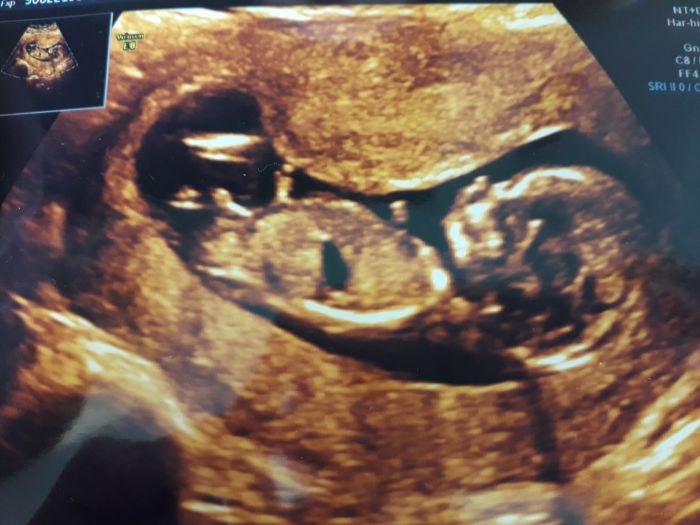

Jinak v úterý jsem byla na běžné kontrole u své doktorky. Poprvé mě zvážili, přibrala jsem už 5 kg! Změřili tlak, krev dopadla prý dobře, cukr mám 4,6, další hodnoty nevím. Doktorka mi udělala už jen vnější kontrolu přes břicho, maličké už vypadá jako miminko a hýbalo se, krásný pohled :-)

A včera jsem byla v Plzni na Screeningu. Je to tam hezké, ale musím říct, že p. doktorka byla dost doměřená, nepříjemná a chtěla to mít rychle za sebou. Na každý můj dotaz se tvářila otráveně, vzala to hodně hopem - tady je noha, tady ruka, tady páteř, tady hlava. Na dotaz jestli už by nebylo trochu vidět pohlaví se tvářila hodně divně a jen řekla - to asi těžko. Zeptala se pouze na to, jestli se v rodině narodilo postižené dítě, pak už se neptala vůbec na nic a nemluvila. Ale pohled na ten maličký zázrak mi to asi vynahradil, bylo to krásné, točil se tam, převaloval a vydržela bych se dívat celý den. Pak mi ještě vzali krev a řekli, že pokud ten den nebudou volat, tak je vše v pořádku a do 2 dnů výsledky pošlou k mé doktorce. Tam jdu na kontrolu až 6.4.

Maminky dnes jsem byla na screeningu a u nás je vse naprosto v pořádku

A budeme mít holčičku